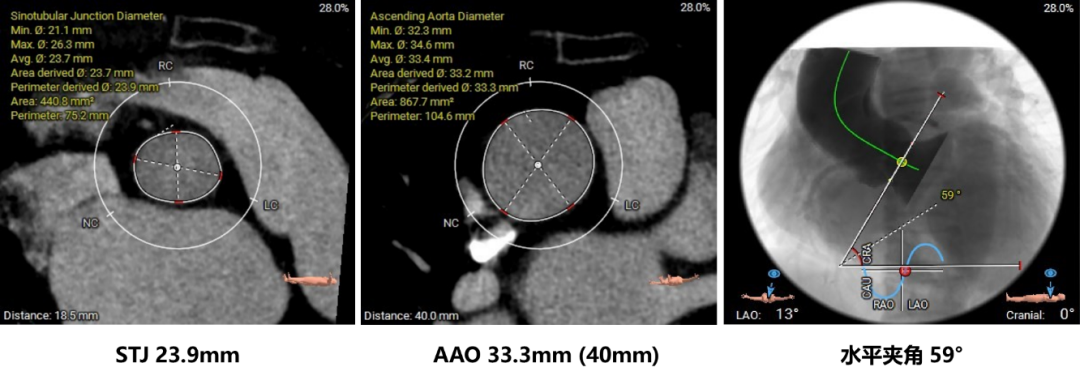

主动脉根部评估:

瓣环上结构测量: